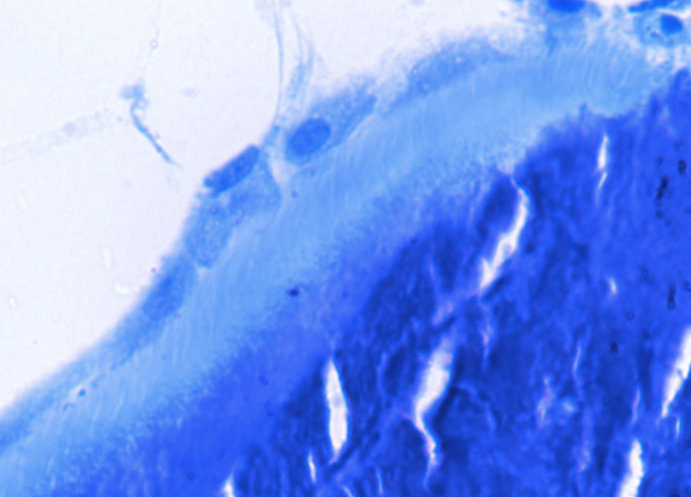

[EWING’S SARCOMA/PNET, BONE] – One of the characteristic features of ES/PNET is the presence of cytoplasmic PAS positive glycogen granules (arrowhead) which dissolves upon treatment with diastase (PAS-D). However, PAS positive cytoplasmic glycogen can be found in some cases of precursor T-cell lymphoblastic lymphoma making the differentiation difficult. In contrast to cases of ES/PNET the cytoplasmic PAS-positive granules are fewer and smaller in lymphoblastic lymphoma. However, the presence of PAS-positive cytoplasmic glycogen helps exclude small cell neuroendocrine carcinomas.